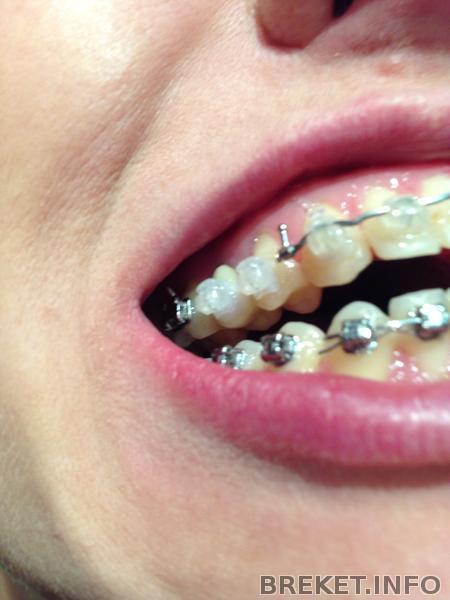

брекеты коронки на верхние единички

Ситуация "до", спустя неделю после установки, спустя два месяца после установки (плюс смена дуги). Прикус прямой.

Первая дуга в сравнении со второй прямоугольной вела себя гораздо "скромнее". Стою в магазине и думаю, что же я хочу съесть на ужин?